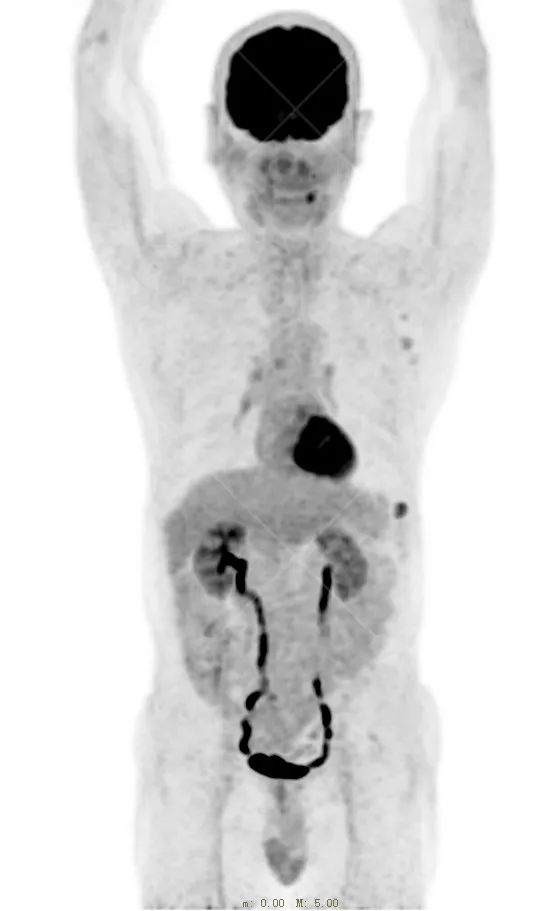

PET/CT 示:

左下胸壁(约左侧第 8 前肋水平)皮肤见一小片状放射性摄取轻度增高影,范围约 0.8 cm×2.2 cm×1.6 cm,SUV 最大值为 3.9,CT 于上述部位见异常软组织密度影,边界尚清,密度尚均匀,CT 值约 40.0 Hu,局部突出体表。

PET/CT 结论:

左下胸壁(约左侧第 8 前肋水平)皮肤小片状代谢轻度增高灶,结合病史,考虑为恶性肿瘤(黑色素瘤)。

病理结果:

符合黑色素瘤(结节型)。